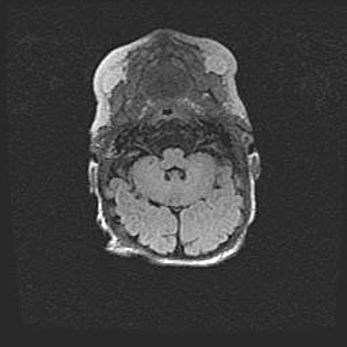

Лейкомаляция с кистозно-глиозной дегенерацией головного мозга.

Возраст: 2 месяца 25 дней

Вес: 6400 г

Окружность головы: 40 см

Срок гестации: 41 неделя

Лейкомаляцию относят к ишемически-гипоксическим повреждениям головного мозга, диагностируемым у новорожденных. При лейкомаляции в головном мозге обнаруживают очаги некроза, возникшие после тяжелой гипоксии и нарушения кровотока. В процессе морфогенеза очаги проходят три стадии: 1) развития некроза, 2) резорбции и 3) формирования глиозного рубца или кисты. Перивентрикулярная лейкомаляция (ПЛ) встречается примерно в 12% случаев среди новорожденных, обычно – у недоношенных детей, причем, частота ее зависит от массы, с которой младенец появился на свет. Наибольшее число малышей страдает лейкомаляцией, если масса при рождении 1500-2500 г.